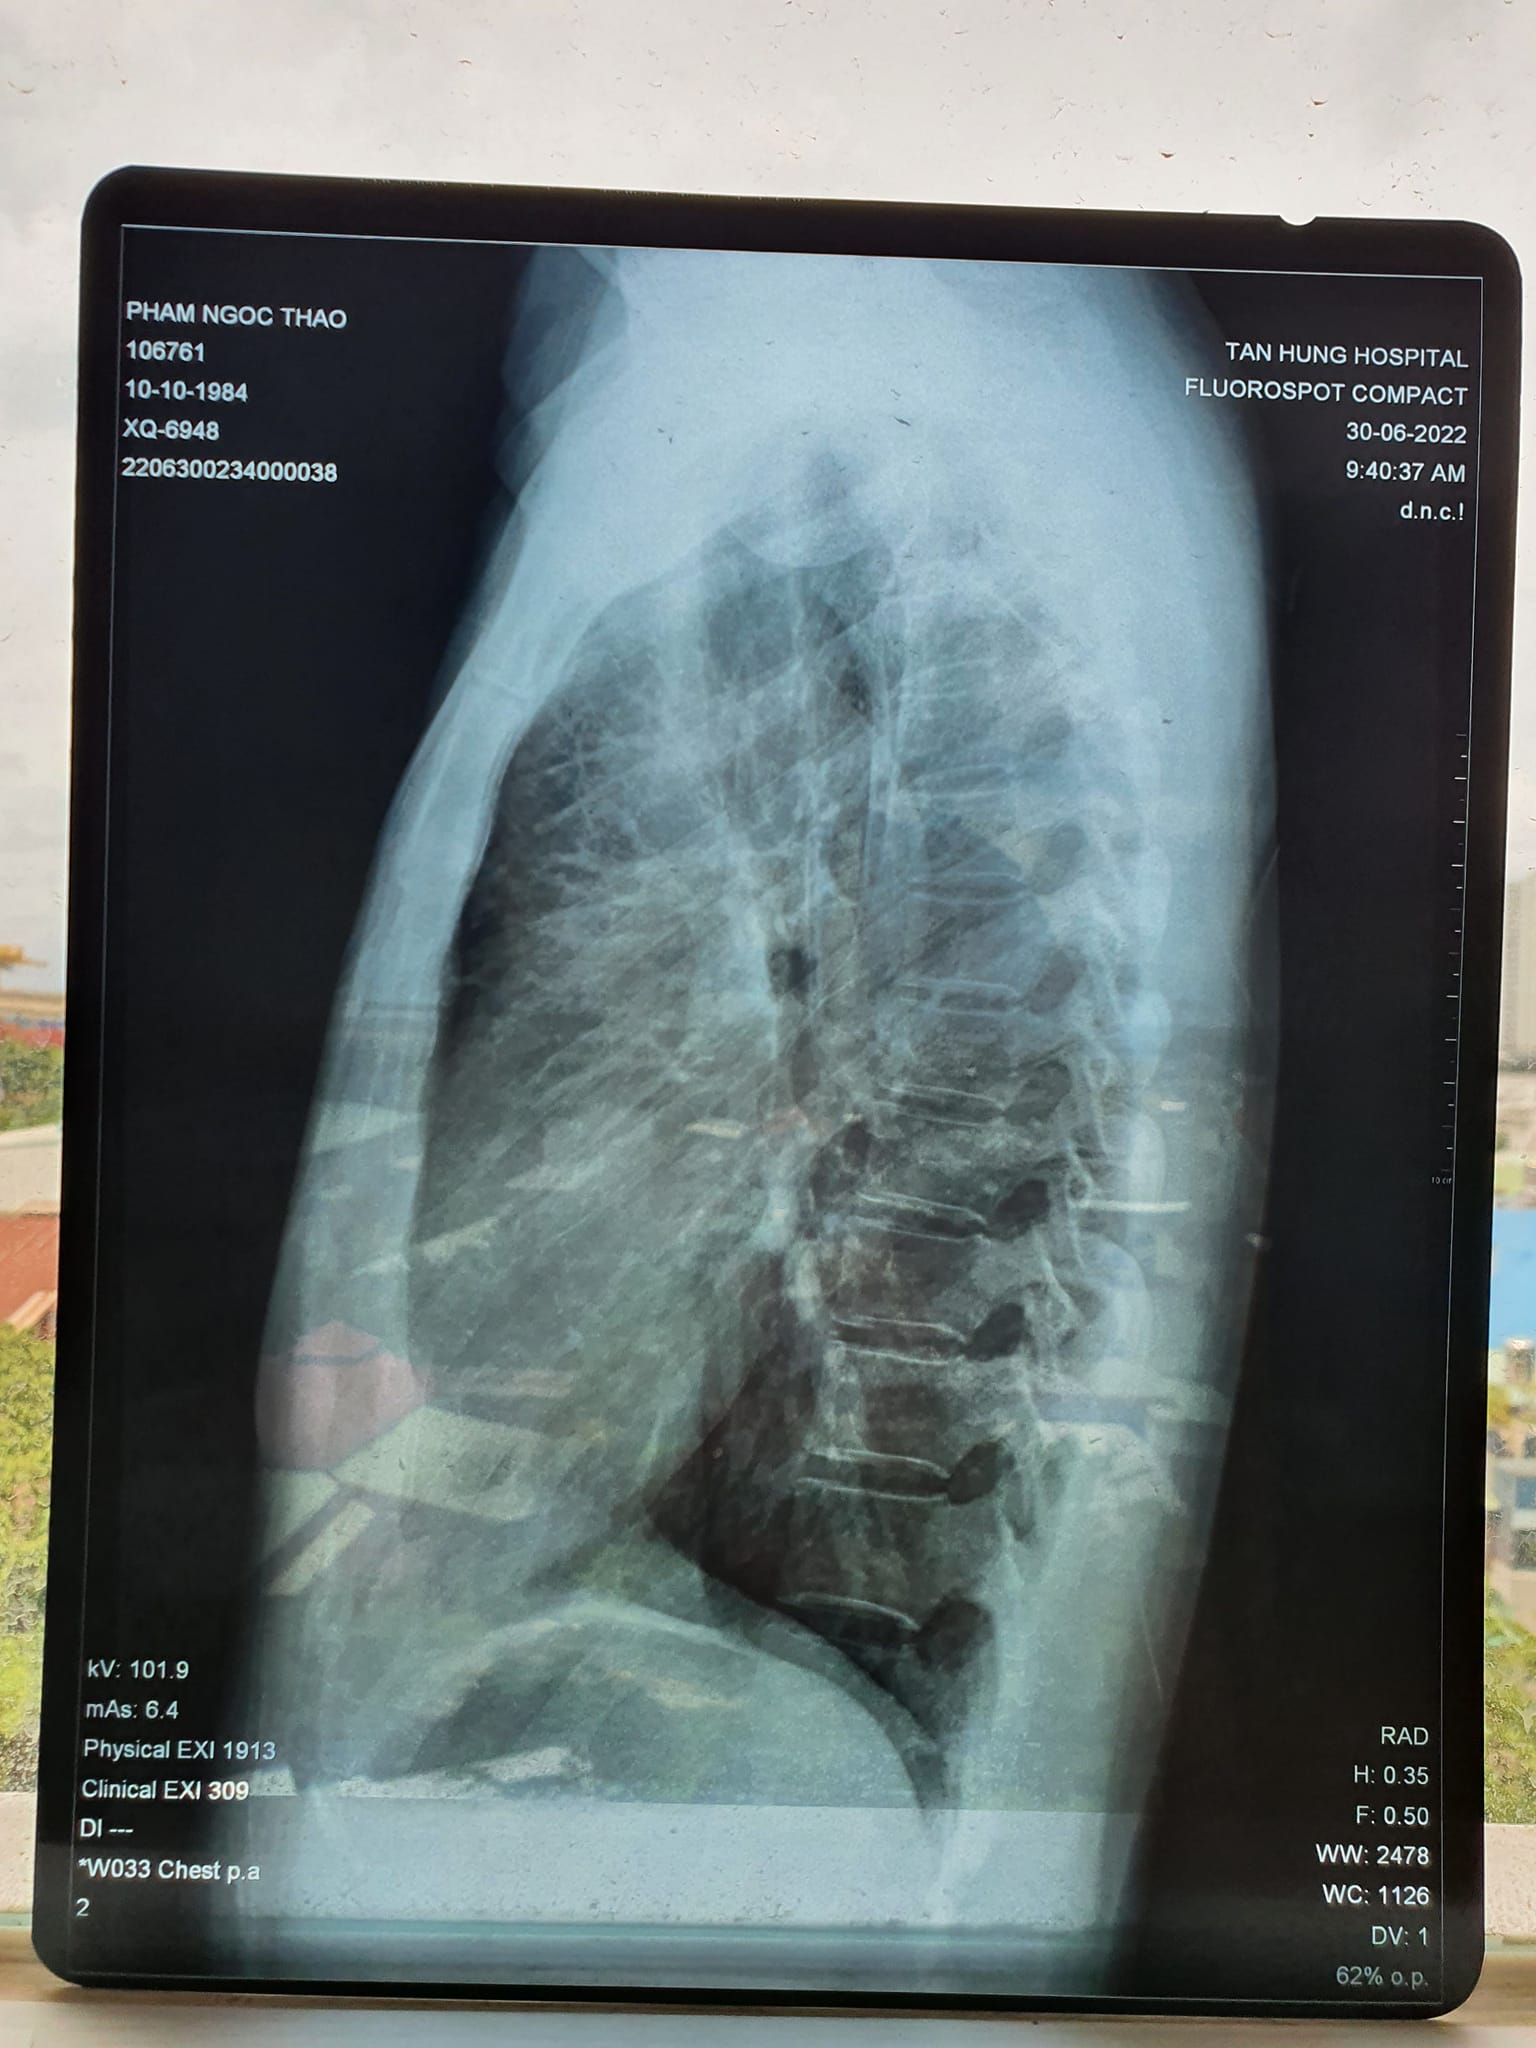

Kết quả X quang và CT sau khi chăm sóc sức khỏe bằng Năng lượng sinh học vào ngày 30/6/2022